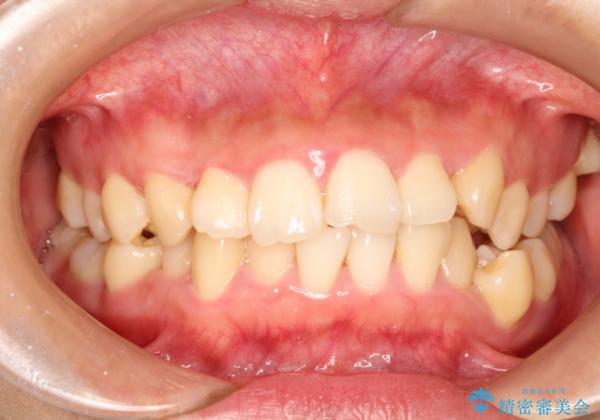

上下の歯のガタガタ ワイヤーでの抜歯矯正で整った歯並びへ

- 上下の歯のガタガタを治したいとのことで来院されました。

がたつきの度合いが強いのと、口元をなるべく引っ込めたい希望がありましたので、ワイヤーでの抜歯矯正となりました。

ガタガタが重度の方は抜歯が必要となることが多いです。

抜歯スペースを使って前歯を引っ込めることにより、口元の突出感も改善できました。